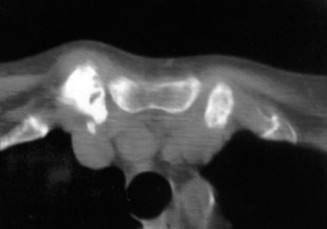

A 24-year-old male presents to your office with a complaint of progressive dull, aching pain in his neck. Rec…